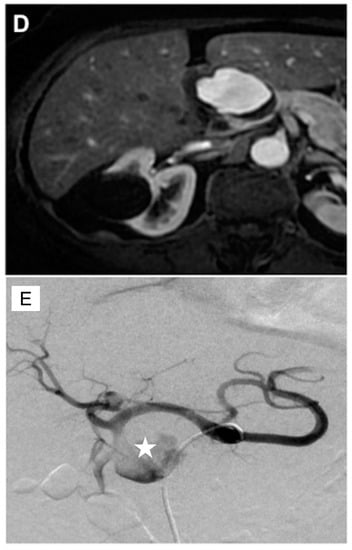

4. GDA Pseudoaneurysm Embolization